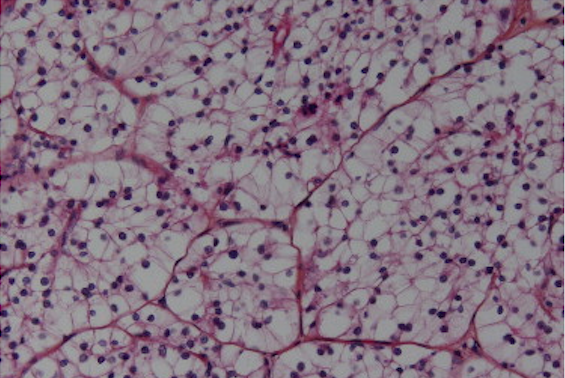

- Carcinome rénal à cellules claires Crédit : Association française d'urologie